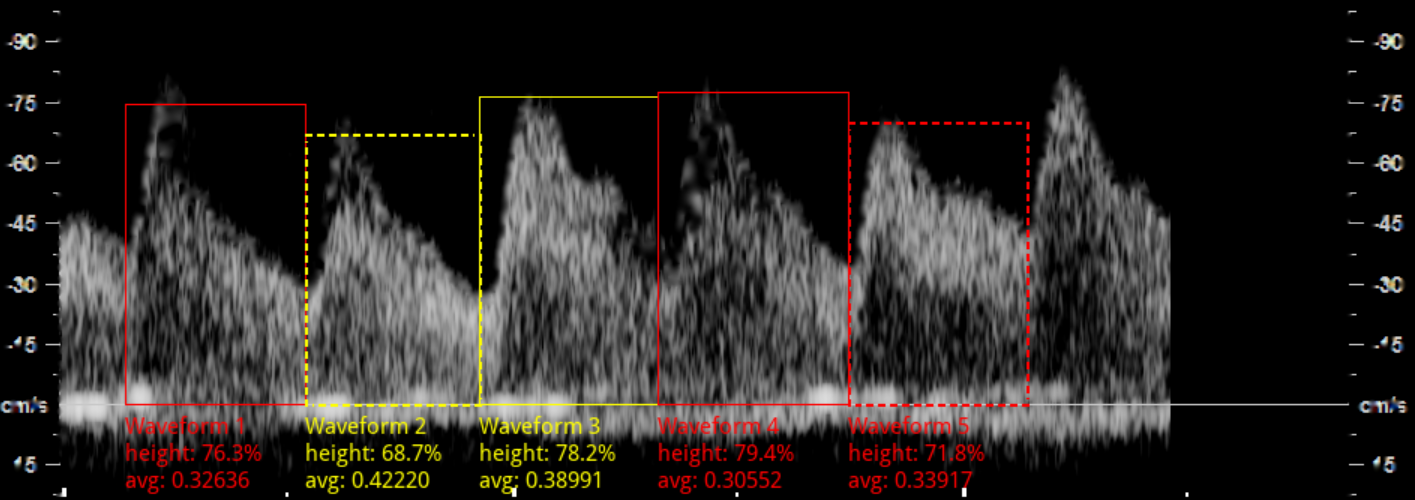

Having identified individual waveforms, we need to quantify their quality in order to assess whether the waveform as a whole satisfies the last three ISUOG criteria. To obtain this, the spectrum image pixels are first rescaled to floating point values between 0 and 1. Using the spectrum segmentation, we mask out the relevant part of the spectrum to compute the mean intensity of pixels in each individual waveform. Two threshold values are defined to classify the waveform as having good, moderate, or poor clarity (see Fig. 5). In our experiment, these thresholds are set empirically to 0.56 and 0.36. Heights of the waveform are determined from the peak coordinate and the x𝑥x-axis line, followed by expressing them as a percentage of the positive y𝑦y-axis.

Refer to caption

Figure 5: Waveform clarity and height. Good clarity is indicated in green (mean intensity > 0.56), moderate in yellow, and poor in red (mean intensity < 0.36) is poor. Dotted line indicates waveforms with height less than 75%.

We applied the proposed waveform quality assessment pipeline on the 657 spectrum images. Fig. 6 presents two images that has failed to meet the ISUOG waveform clarity and dynamic range criteria, identified by our method. This demonstrates the promising potential of our pipeline being alternatively deployed as a retrospective waveform quality assessment tool.

(a) Less than 3 consecutive waveforms with at least moderate clarity

(b) Waveforms not occupying 75% of the y-axis

Figure 6: Example spectrums not meeting the ISUOG criteria. Zoom in for details.